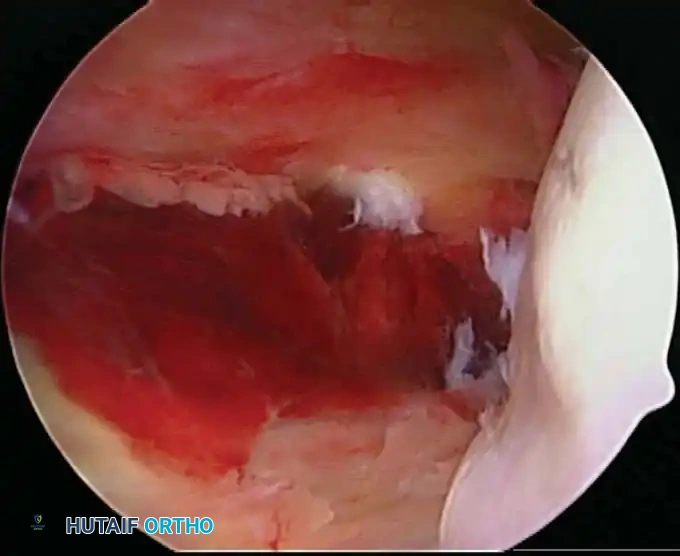

Once diagnostic evaluation is complete and hemostasis is secured, the therapeutic phase commences. Whether performing a SLAP repair, a Bankart stabilization, or a rotator cuff repair, the principles of tissue mobilization, anatomical footprint restoration, and secure biomechanical fixation remain paramount.

Modern arthroscopy relies heavily on suture anchors (biocomposite or all-suture constructs) and advanced arthroscopic knot-tying or knotless techniques. The ability to pass sutures through retracted, fibrotic tissue and secure them under appropriate tension without strangulating the microvascular supply is the hallmark of a master arthroscopist.